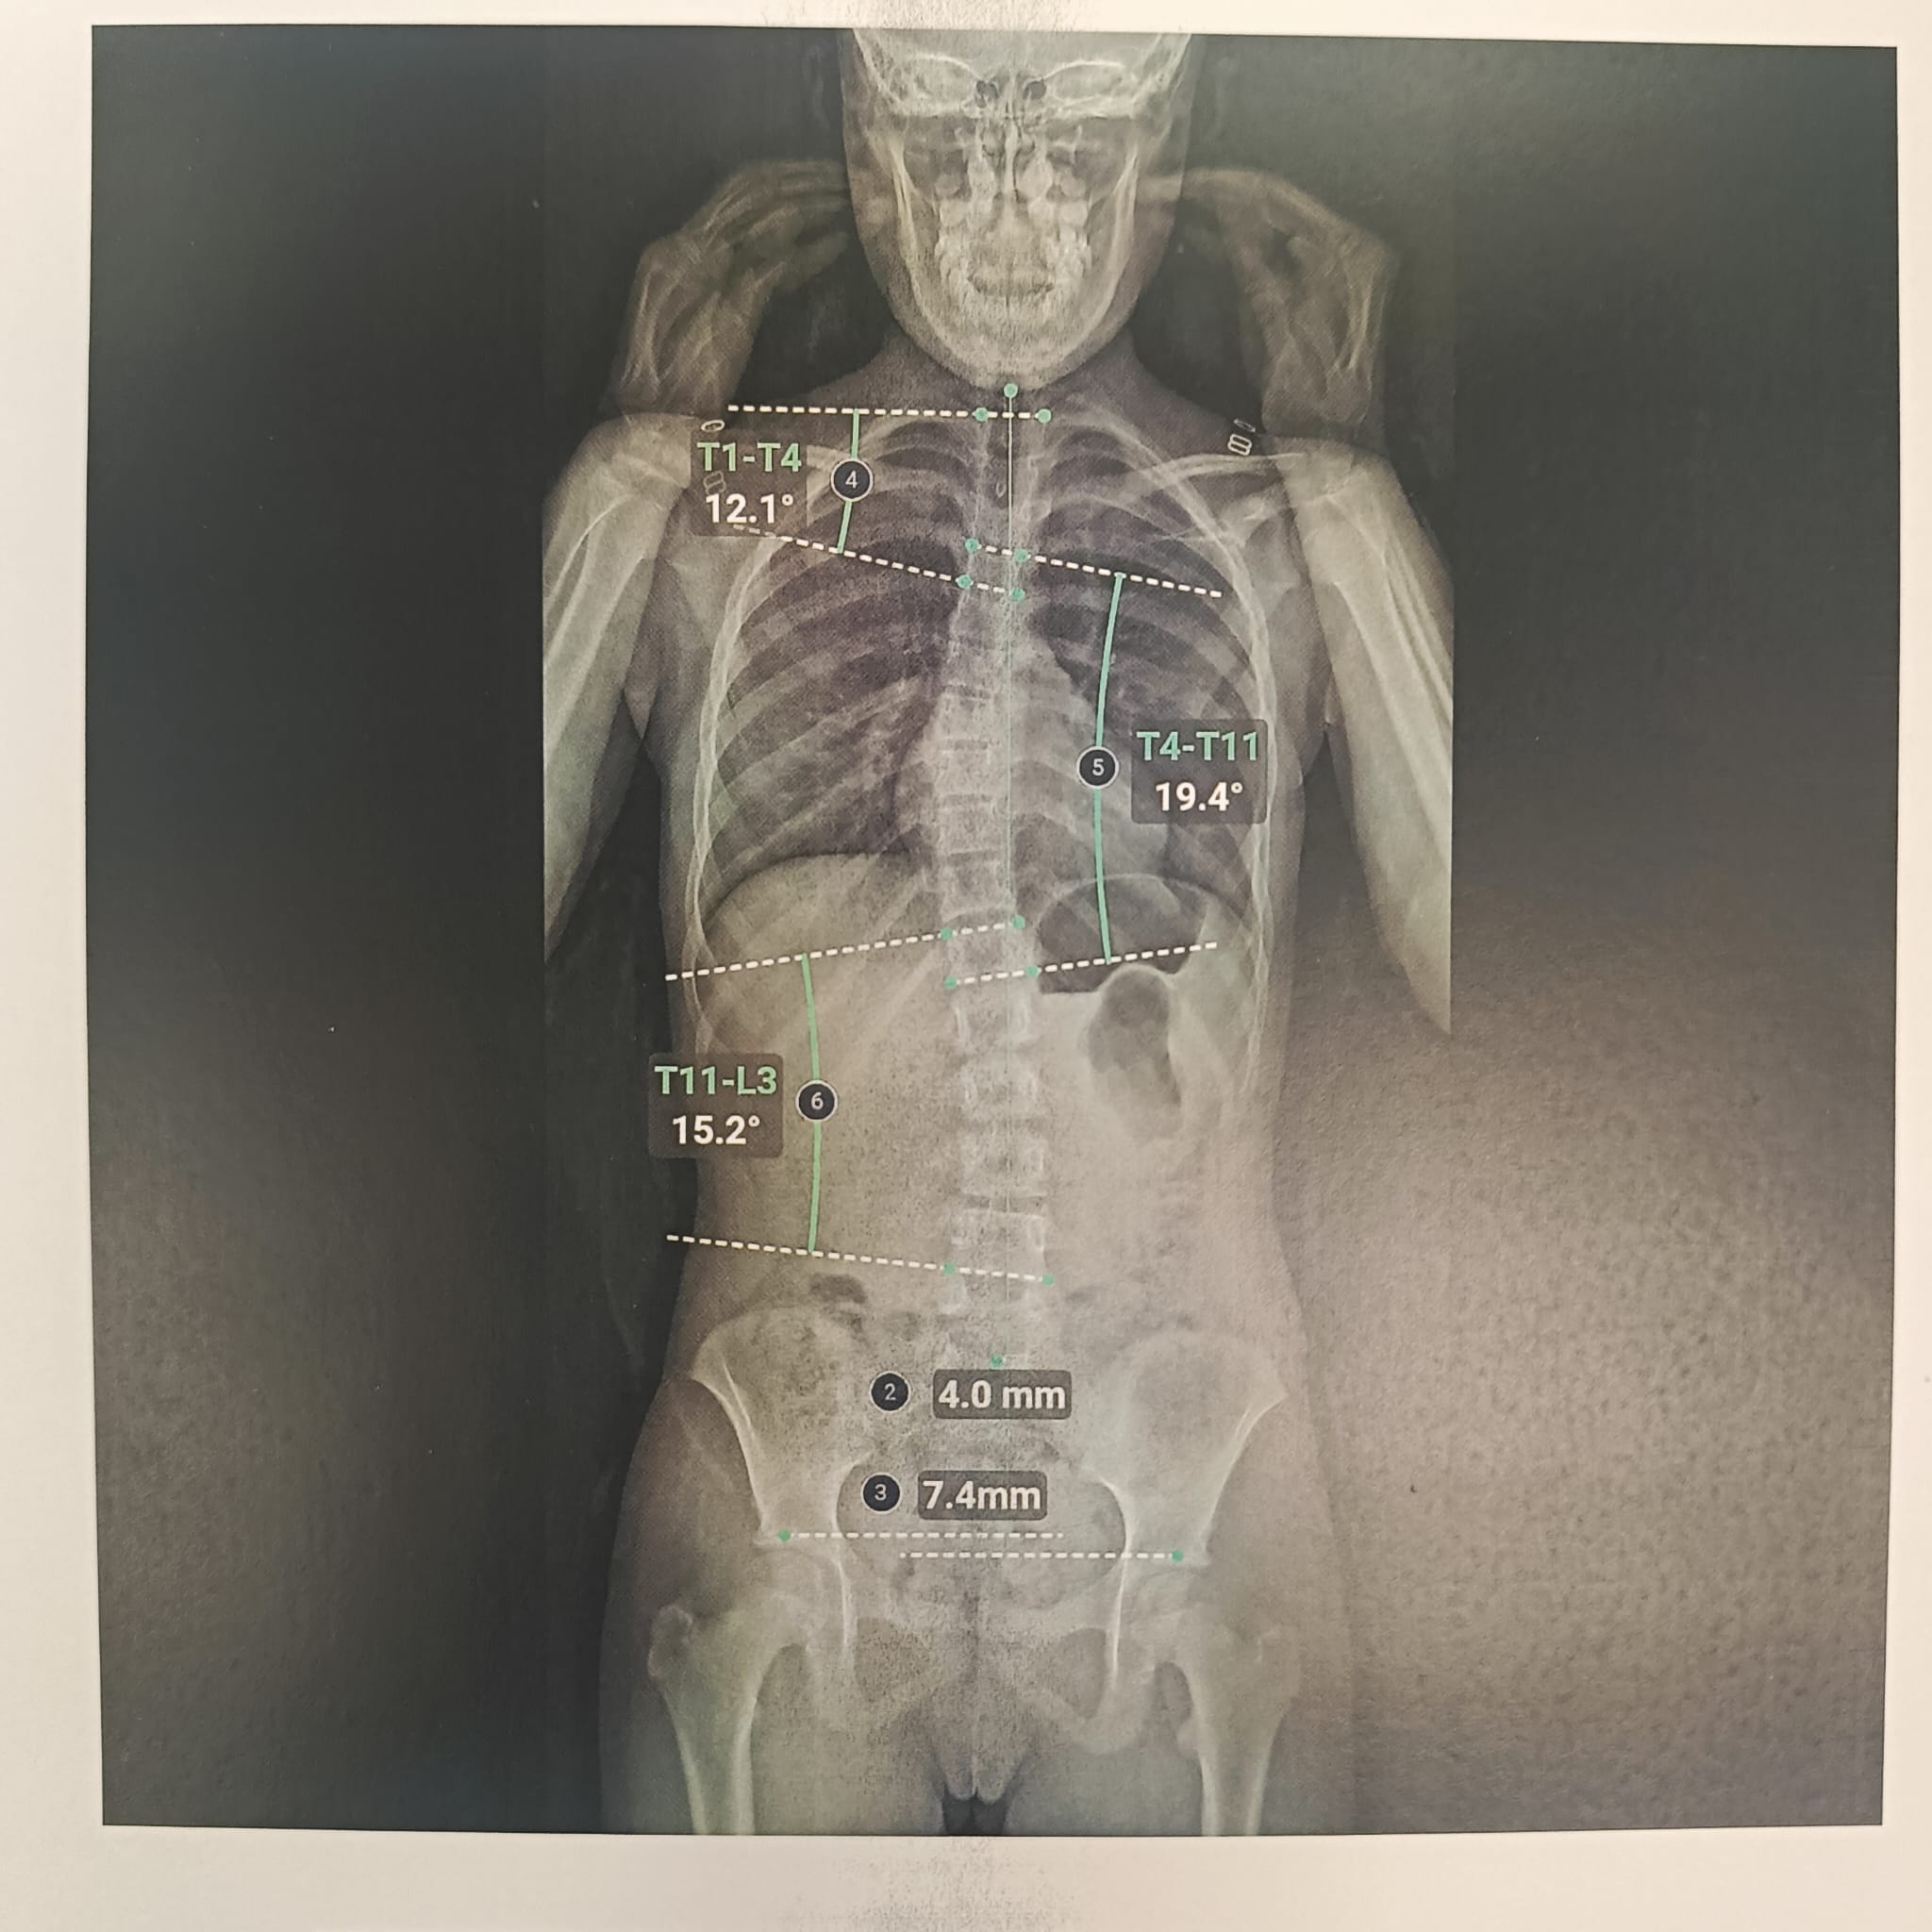

La scoliose est une déviation de la colonne vertébrale dans les 3 plans de l’espace. Celle-ci amène une silhouette asymétrique (visible au niveau des épaules et de la taille) et l’apparition de gibbosités (bosse), ainsi qu’un déséquilibre et une limitation de mouvement du tronc. Dans certains cas graves, la capacité respiratoire du patient peut se trouver limitée.

Le traitement se fait par appareillage au moyen d’un corset orthopédique sur mesure, moulé sur le corps et conçu de manière à permettre une croissance normale du rachis en corrigeant les déformations existantes.

Chaque corset est réalisé et adapté selon la morphologie du patient. Il tient compte de la déformation du rachis, du poids et de la taille de celui-ci, ainsi que de la prescription médicale. Selon la déformation du rachis et le modèle de corset prescrit, les temps de port de ce dernier peuvent être variables. De même des ajustements peuvent être réalisés selon l’évolution de la pathologie et de la morphologie du patient.